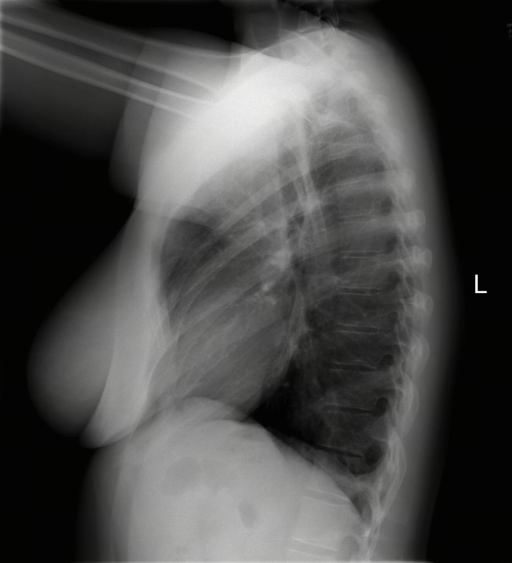

While anatomical reasoning provides the logical framework, visual limitations can hinder fine-grained detection. To address this, we integrated Think with Image [67, 22] design, enabling the model to perform secondary operations—such as rotating or zooming in—to facilitate a deeper understanding of visual information. This capability holds tremendous potential in medical imaging; for instance, zooming in on affected regions allows the model to perform granular inspection. Through exploration of tools in the multimodal domain, we identified Zoom in and Rotate as the most valuable primitives: the former is primarily designed for identifying subtle lesions in affected regions, while the latter assists with maintaining spatial orientation during the interpretation of complex medical images.

The training dataset is built mainly from radiology imaging data (e.g., X-rays, CT scans, MRI) and public de-identified radiology datasets, which include pathological/normal cases, metadata and expert annotations. Given the varying diagnostic complexity and tool utility of raw radiology data, a two-stage filtering pipeline is adopted to create an effective RL training set: